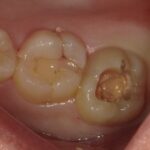

歯を削っていくとかなり茶色くなり虫歯に罹患しています。

特に奥歯の場合、このように見た感じ虫歯に見えない場合が

よくあります。しかし歯の表面のエナメル質は骨より硬く

虫歯菌の出す酸では容易には溶けません。しかし甘い食べ物が

多いなどリスクが高まりますとエナメル質は溶け、その中の

象牙質はエナメル質より柔らかいためこのように「アリの巣」の

ように中で大きくなってしまうのです。